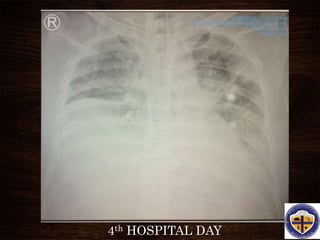

4th HOSPITAL DAY

• #41 A representative anteroposterior chest x-ray in the exudative phase of ARDS shows diffuse interstitial and alveolar infiltrates that can be difficult to distinguish from left ventricular failure.